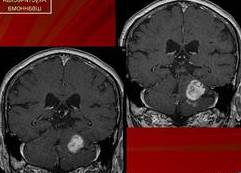

Доброкачественная опухоль мозга, по мнению врачей, представляет собой образование, которое не проникает в окружающие ткани и не метастазирует. Обычно такие опухоли имеют четкие границы и медленно растут. Врачи отмечают, что симптомы могут варьироваться в зависимости от локализации опухоли, но часто включают головные боли, изменения в зрении, слухе или координации. На МРТ доброкачественные опухоли выглядят как яркие участки с четкими контурами, что позволяет легко их отличить от злокачественных образований. Важно отметить, что даже доброкачественные опухоли могут вызывать серьезные проблемы, если они оказывают давление на жизненно важные структуры мозга. Поэтому регулярные обследования и консультации со специалистами крайне важны для своевременной диагностики и лечения.

Как выглядит доброкачественная опухоль на МРТ?

Доброкачественная опухоль на МРТ. Однородная структура. Четкие, ровные контуры. Отсутствие перифокального отека. Слабое по сравнению со злокачественной опухолью накопление контрастного вещества (менее яркая).